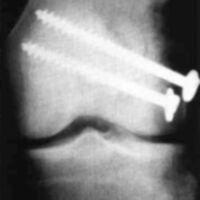

A nineteen year old male sustained a distal fracture with a split condylar fracture to the right leg (Fig. 10) and a lateral condyle fracture on the contralateral side (Fig. 11). Fractures were stabilized, but were not internally fixed at time of admission because of emergency vascular repairs being required. Three days post injury, the patient underwent ORIF of his fractures (Fig. 12 and Fig. 13). The right leg was placed in a free knee Mobilizing Brace and the left leg was placed in the rehabilitative free knee orthosis. A continuous passive motion dynamic suspension system was placed on the lower right extremity (Fig. 14). The lower left extremity had normal pain free motion following surgery. The patient was kept in passive motion for five days and achieved 0-100° of pain free motion. A cast brace was applied on the right extremity; the patient received gait training and was discharged.

Figure 12:

Figure 13: